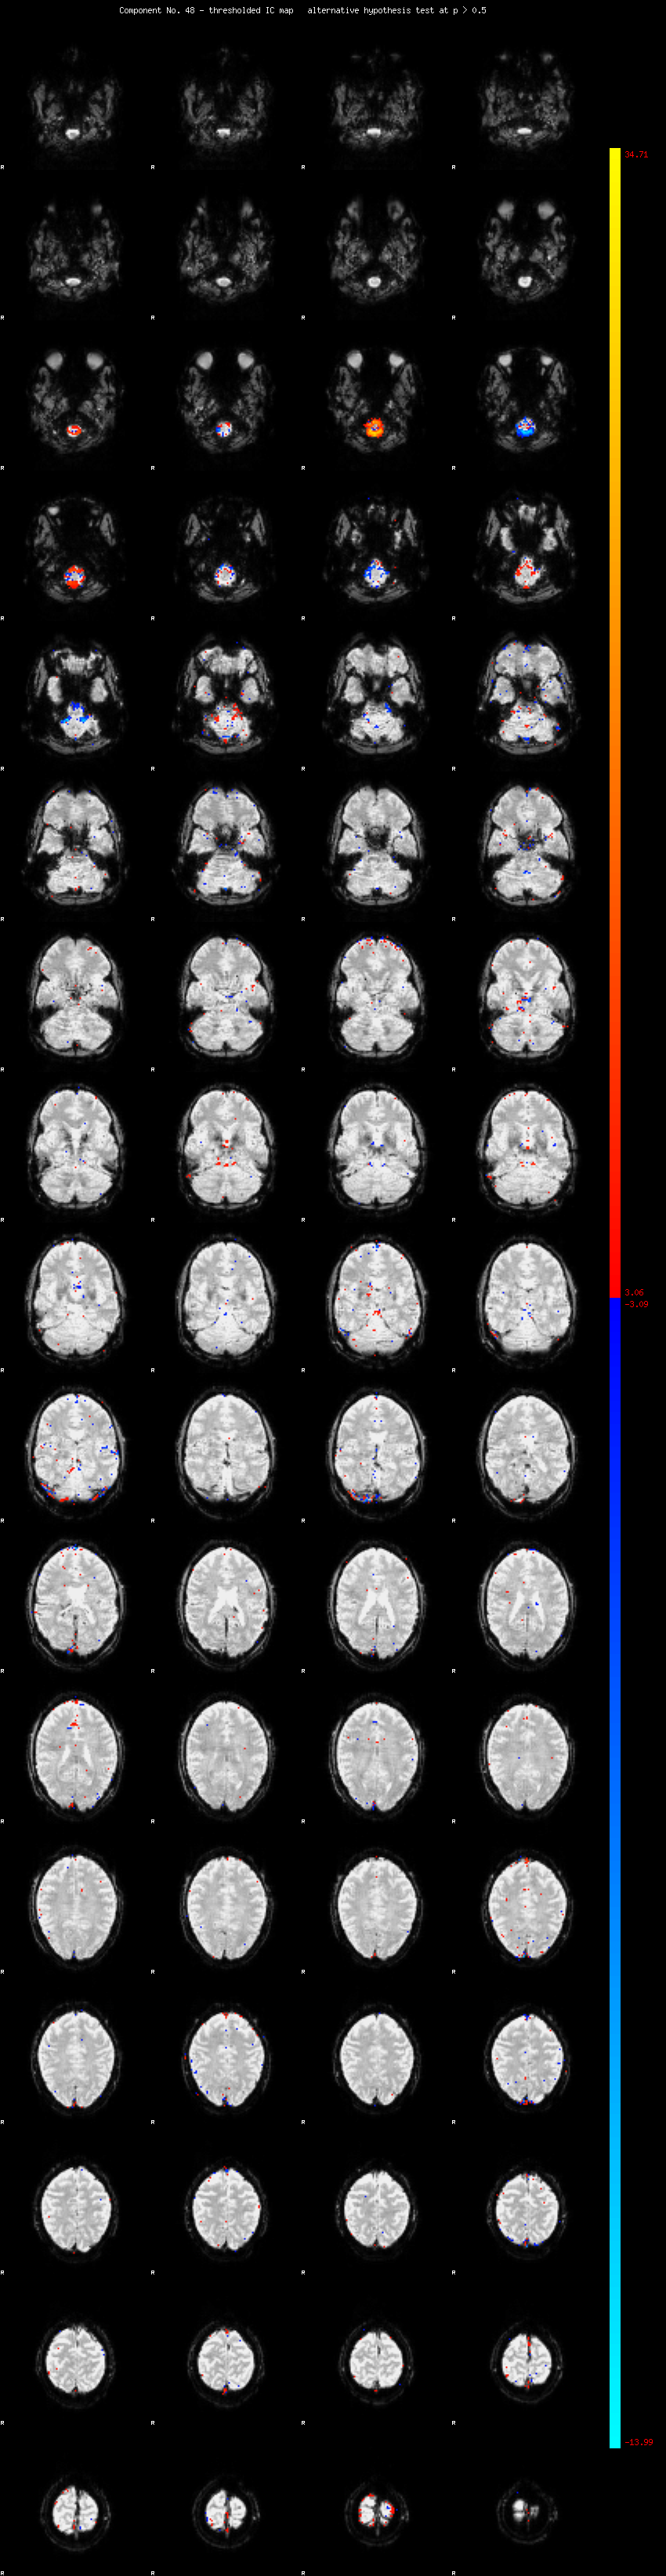

MELODIC Component 48

0.99 % of explained variance;     0.66 % of total variance

MMfit